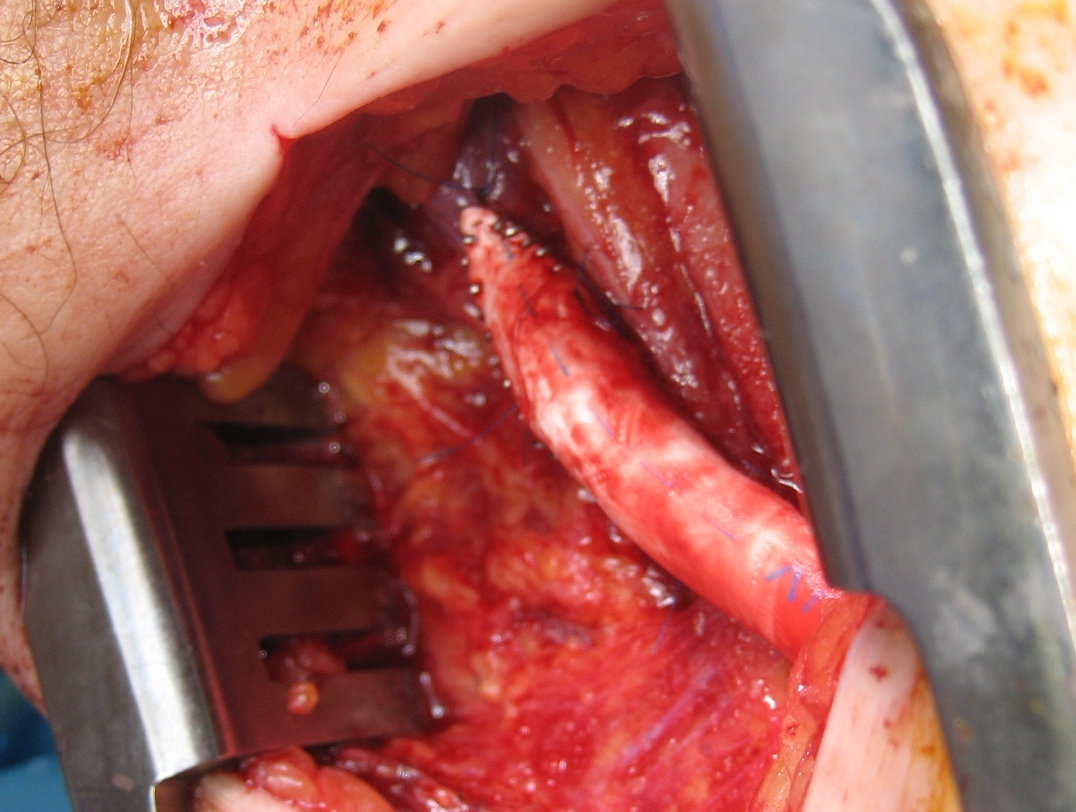

A curvilinear incision (lazy S) was made across the popliteal fossa and careful dissection revealed the aneurysm. It was soft and the vein was normal below in the calf. Above it, there was a tight fibrous band that was contricting it -a popliteal venous entrapment. I released this band. Using a 24 French Foley catheter inserted through a transverse venotomy on the popliteal vein below, the aneurysm was plicated to approximately 1cm diameter, and the catheter removed and the venotomy repaired.

The nerves were restored to their original position and the wound closed in layers. She recovered well and returned to followup about a month later. Duplex showed a patent vein and she had no symptoms of dyspnea.